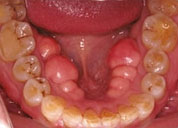

- ATTRITION

- 歯の咬耗(こうもう)

- 下顎前歯の咬耗

- かぶせ物の咬耗

- 奥歯の咬耗